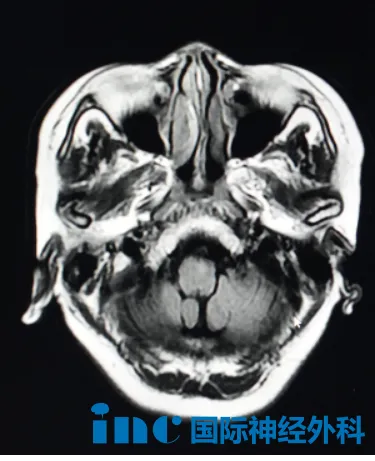

病例详情二:57岁女性桥脑腹侧及中脑脚间窝占位性病变

从右腿无力、“脚踩棉花感”开始,57岁赵女士的平静生活被彻底打破。初诊发现桥脑病变与小脑脂肪瘤时,医生建议“随访观察”。短短6个月,她的身体状况急剧恶化:出现右腿跛行、右臂痉挛,曾经灵活的右手连基本活动都变得困难。复查后医生考虑桥脑腹侧、中脑脚间窝胶质瘤可能性,不建议手术,推荐放化疗。此时患者及家属充满无助与疑问:究竟为何种疾病?是否需要接受盲目放化疗?

然而,巴教授的评估带来了重大转折:中脑部位病灶并非肿瘤,更符合炎症性病变特征。他建议进一步行脑部核磁检查以观察变化。对于小脑脂肪瘤,巴教授认为无需处理,定期观察即可。这一完全不同的诊断结果为家庭指明了新方向。